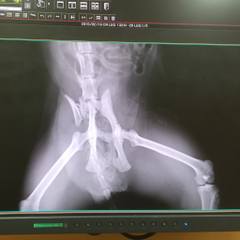

2012年 6月産まれ お外でママのオッパイを吸ってた生後1ヶ月のとらと出会った 毎日ゴハンをあげに通ってたら 3年後・・車にはねられてた 道路脇に倒れてて、下半身が全く動かない状態だった 🏥骨盤骨折・・2ヶ月間の入院 毎日面会にちゅ〜る を持っていった 排便も自力で出来るようになり無事に退院 退院後に一度 元の場所に戻すと元気よく歩いたのに、高い所へのジャンプで滑りおちるのを見て『お外の生活はキツイな💧』と思い連れてかえる 2015月 3月31日 ウチノコ記念日